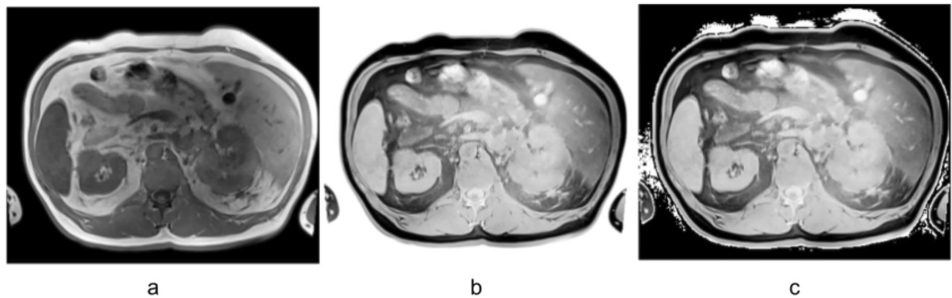

研究团队采用了几项关键技术方法:首先收集了包含1,012例CT扫描和100例患者配对的T1加权(T1w)与T2加权脂肪饱和(T2wfs)MRI序列的数据集;开发了特定的图像反转预处理算法,将MRI强度值进行反转并将背景设置为零;利用两个CT训练模型(TotalSegmentator-fast和多类别肾肿瘤模型)在原始和反转后的MRI图像上进行推理测试;最后使用Dice相似系数(DSC)定量评估分割质量,并通过统计检验分析预处理策略的有效性。

对比反转预处理显著提高了T1w图像所有类别的分割质量(图1)。20个类别的DSC介于0.40(右肾上腺)到0.77(右肾)之间。尽管仍有改善空间,但分割效果最差的出现在左右肺(DSC 0.15、0.16)、胆囊(DSC 0.23)和椎骨(DSC 0.26)。所有类别的平均DSC从0.04增加到0.53。

对于T2加权图像,数据增强导致所有类别的分割质量下降,仅主动脉例外(DSC从0.17提高到0.30)。在所有情况下,未设置背景为零的普通反转效果均不如设置背景为零的反转方法。